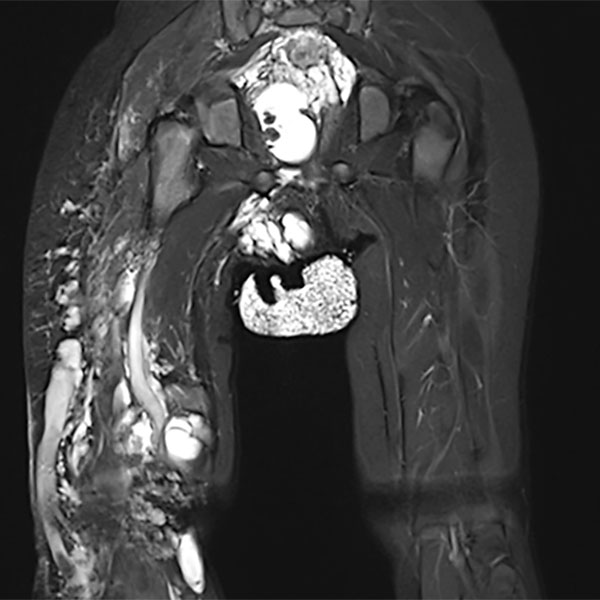

Coronal T2-weighted, fat-suppressed MRI of the pelvis and thighs shows the large extension of the malformation. Multiple sections with microcystic and macrocystic lymphatic malformation components. In addition, an extensive venous malformation with a large marginal vein laterally on the right thigh.

The corresponding axial, T2-weighted, fat-suppressed MRI of the pelvis at the level of the buttocks shows the massive extension especially of the lymphatic malformation in the right gluteal area. Additionally, persistent embryonic sciatic vein in the sense of a venous malformation is depicted.